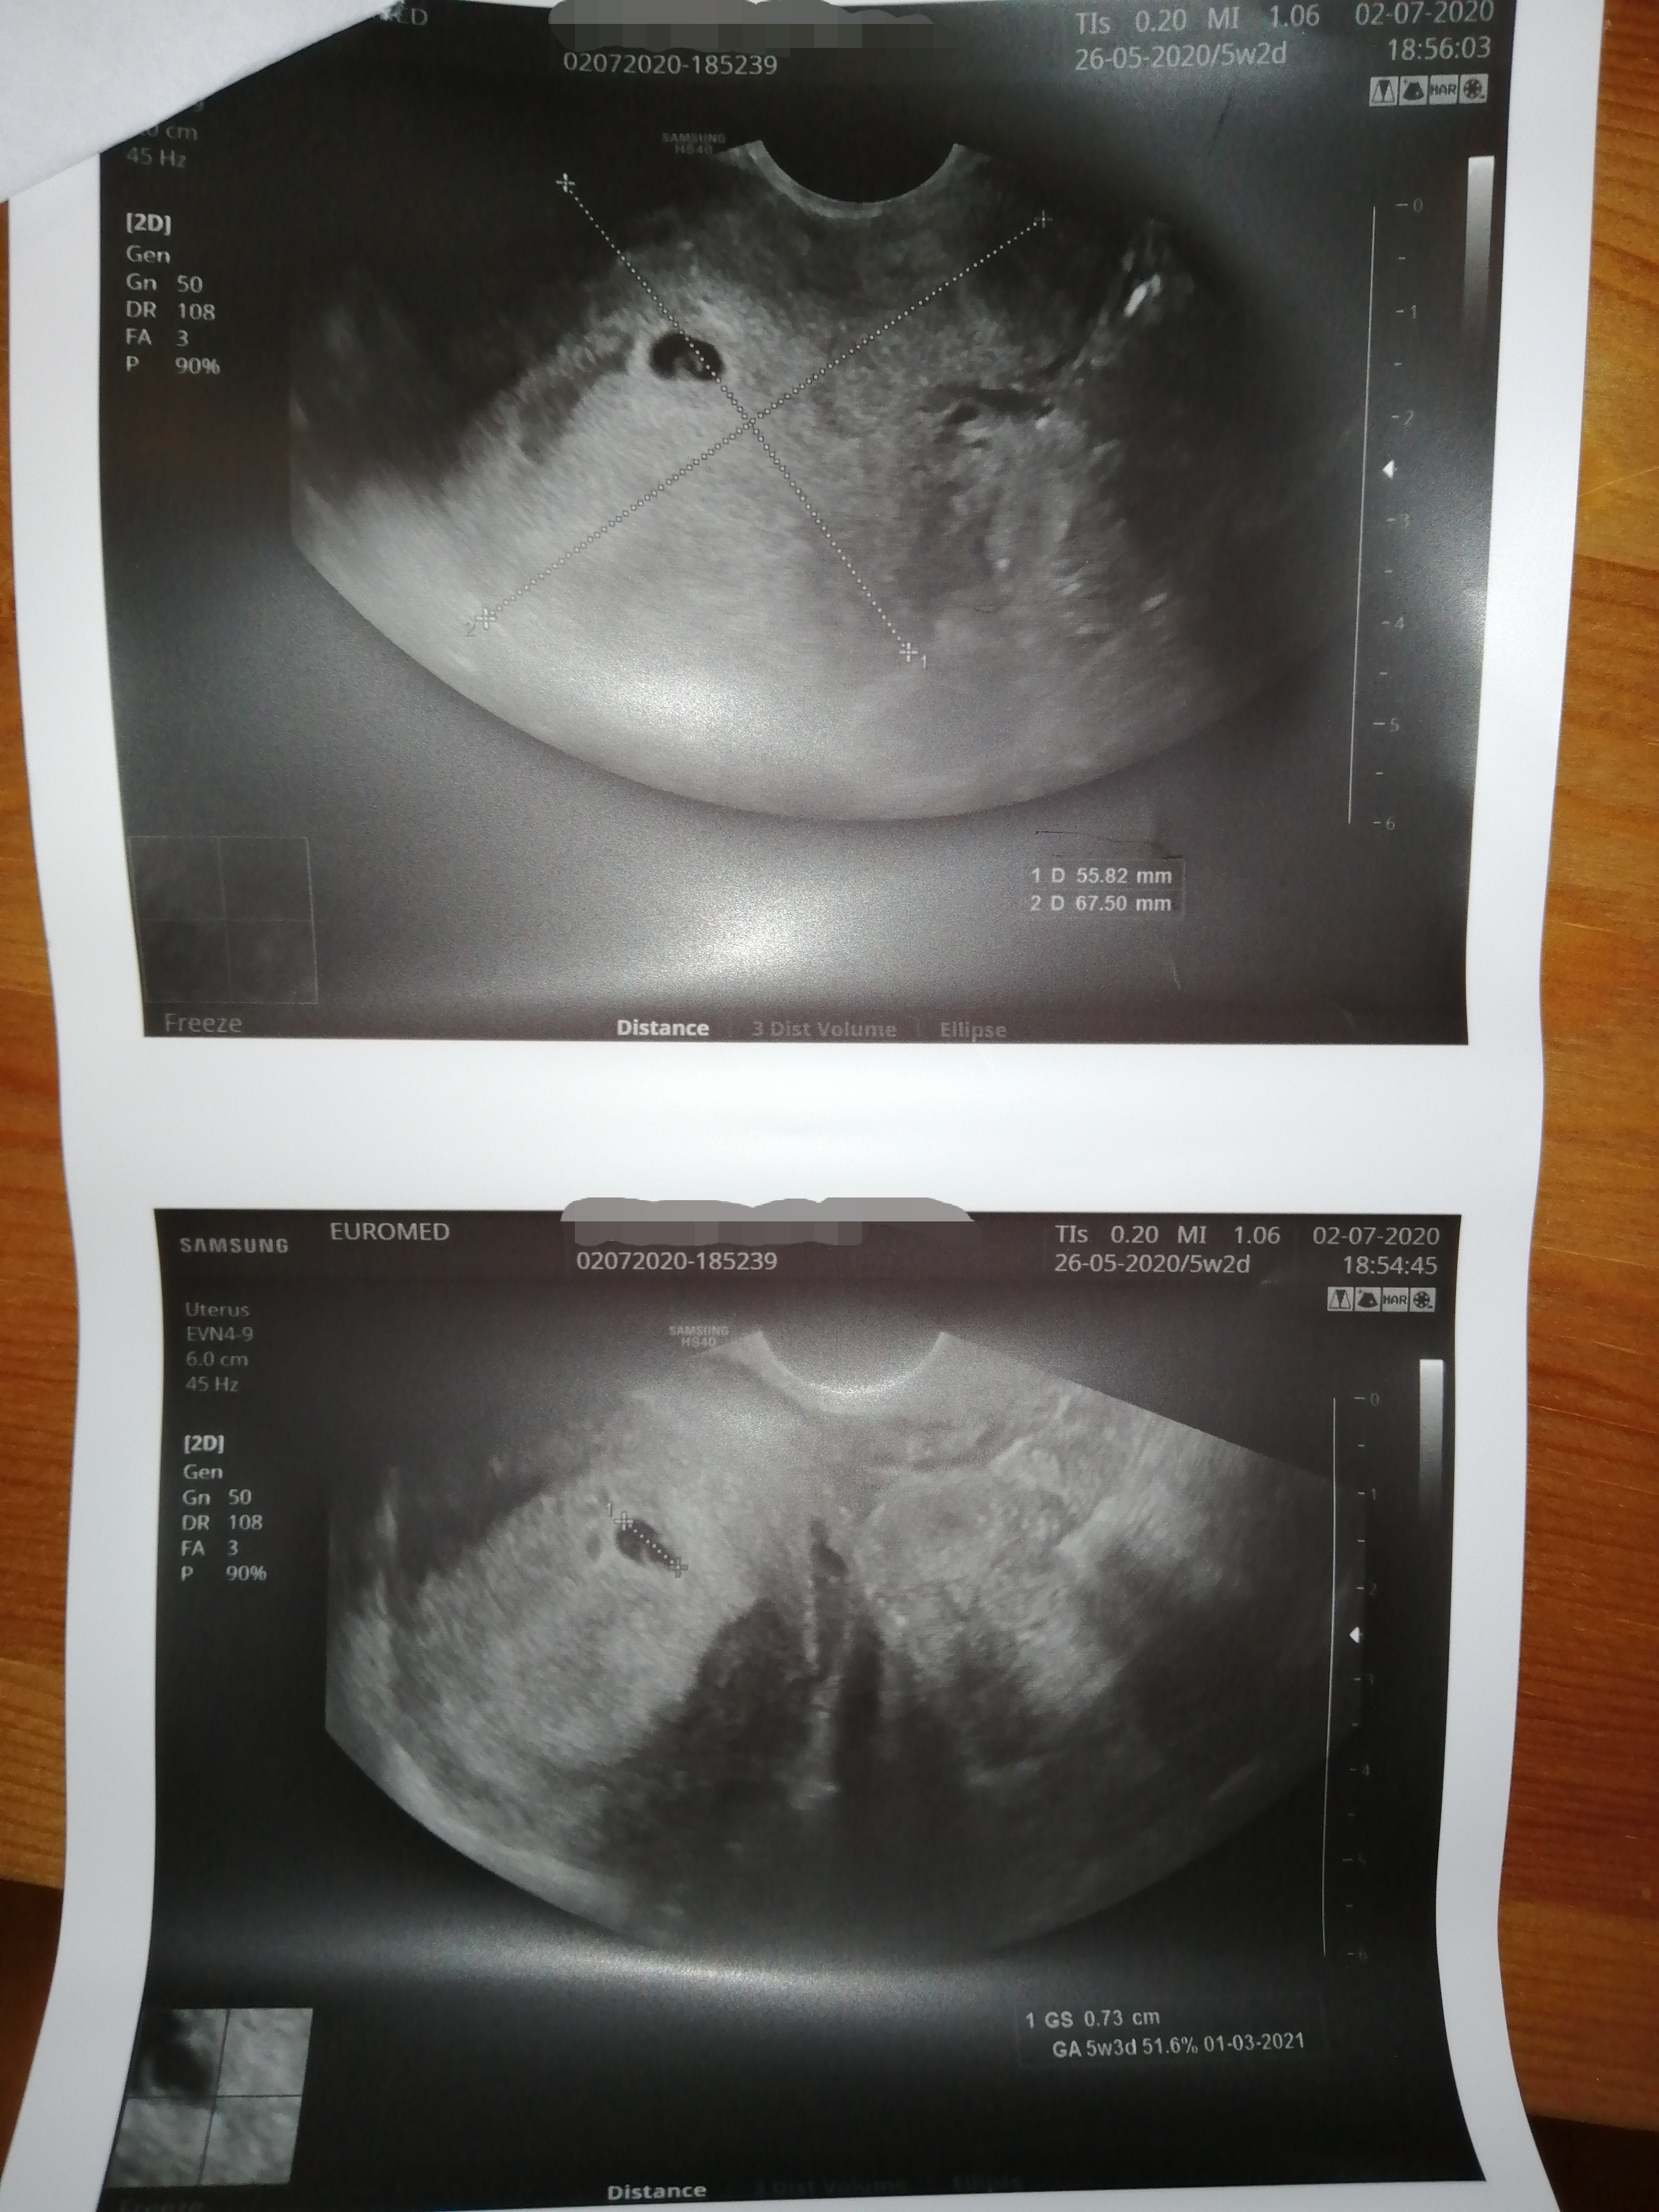

Ja właśnie wróciłam od ginekologa i widziałam moją malutką Fasolkę 😍😍😍 na tym etapie ciąży wszystko jest w najlepszym porządku, następna wizyta za 3 tygodnie ☺️

• IMG_20200702_193825.jpg

IMG_20200702_193825.jpg

1,6 MB · Wyświetleń: 130